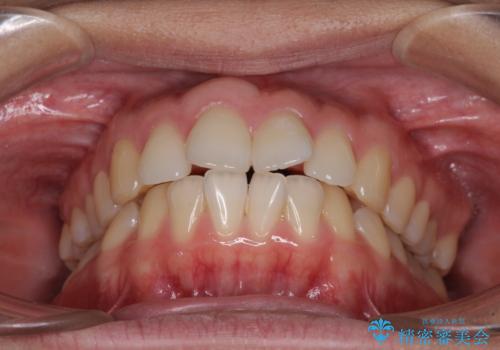

- 前歯の出っ歯と口元の閉じにくさを気にして来院された患者様です。

口元を積極的に引っ込めるために、上下左右の小臼歯4本を抜歯することとしました。

4本の歯を抜歯したことで、飛び出していた口元が引っ込み、横顔が大きく改善されました。